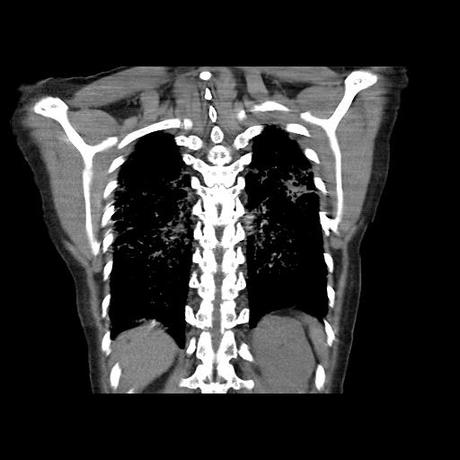

Se realiza volumen de tórax en fase simple, desde los opérculos torácicos hasta los hemidiafragmas, observándose:

El parénquima pulmonar con areas parcheadas difusas en vidrio despulido combinadas con otras areas hipodensas de baja atenuación debidas a atrapamiento aéreo y engrosamiento intersticial y zonas de fibrosis de predominio en lóbulos medios e inferiores de ambos pulmones.

- LOS HALLAZGOS PUEDEN ESTAR EN RELACIÓN A NEUMOPATIA INTERSTICIAL PROBABLE ETIOLOGIA HIPERSENSITIVA VS AUTOINMUNE/BACTERIANA/FUNGICA.